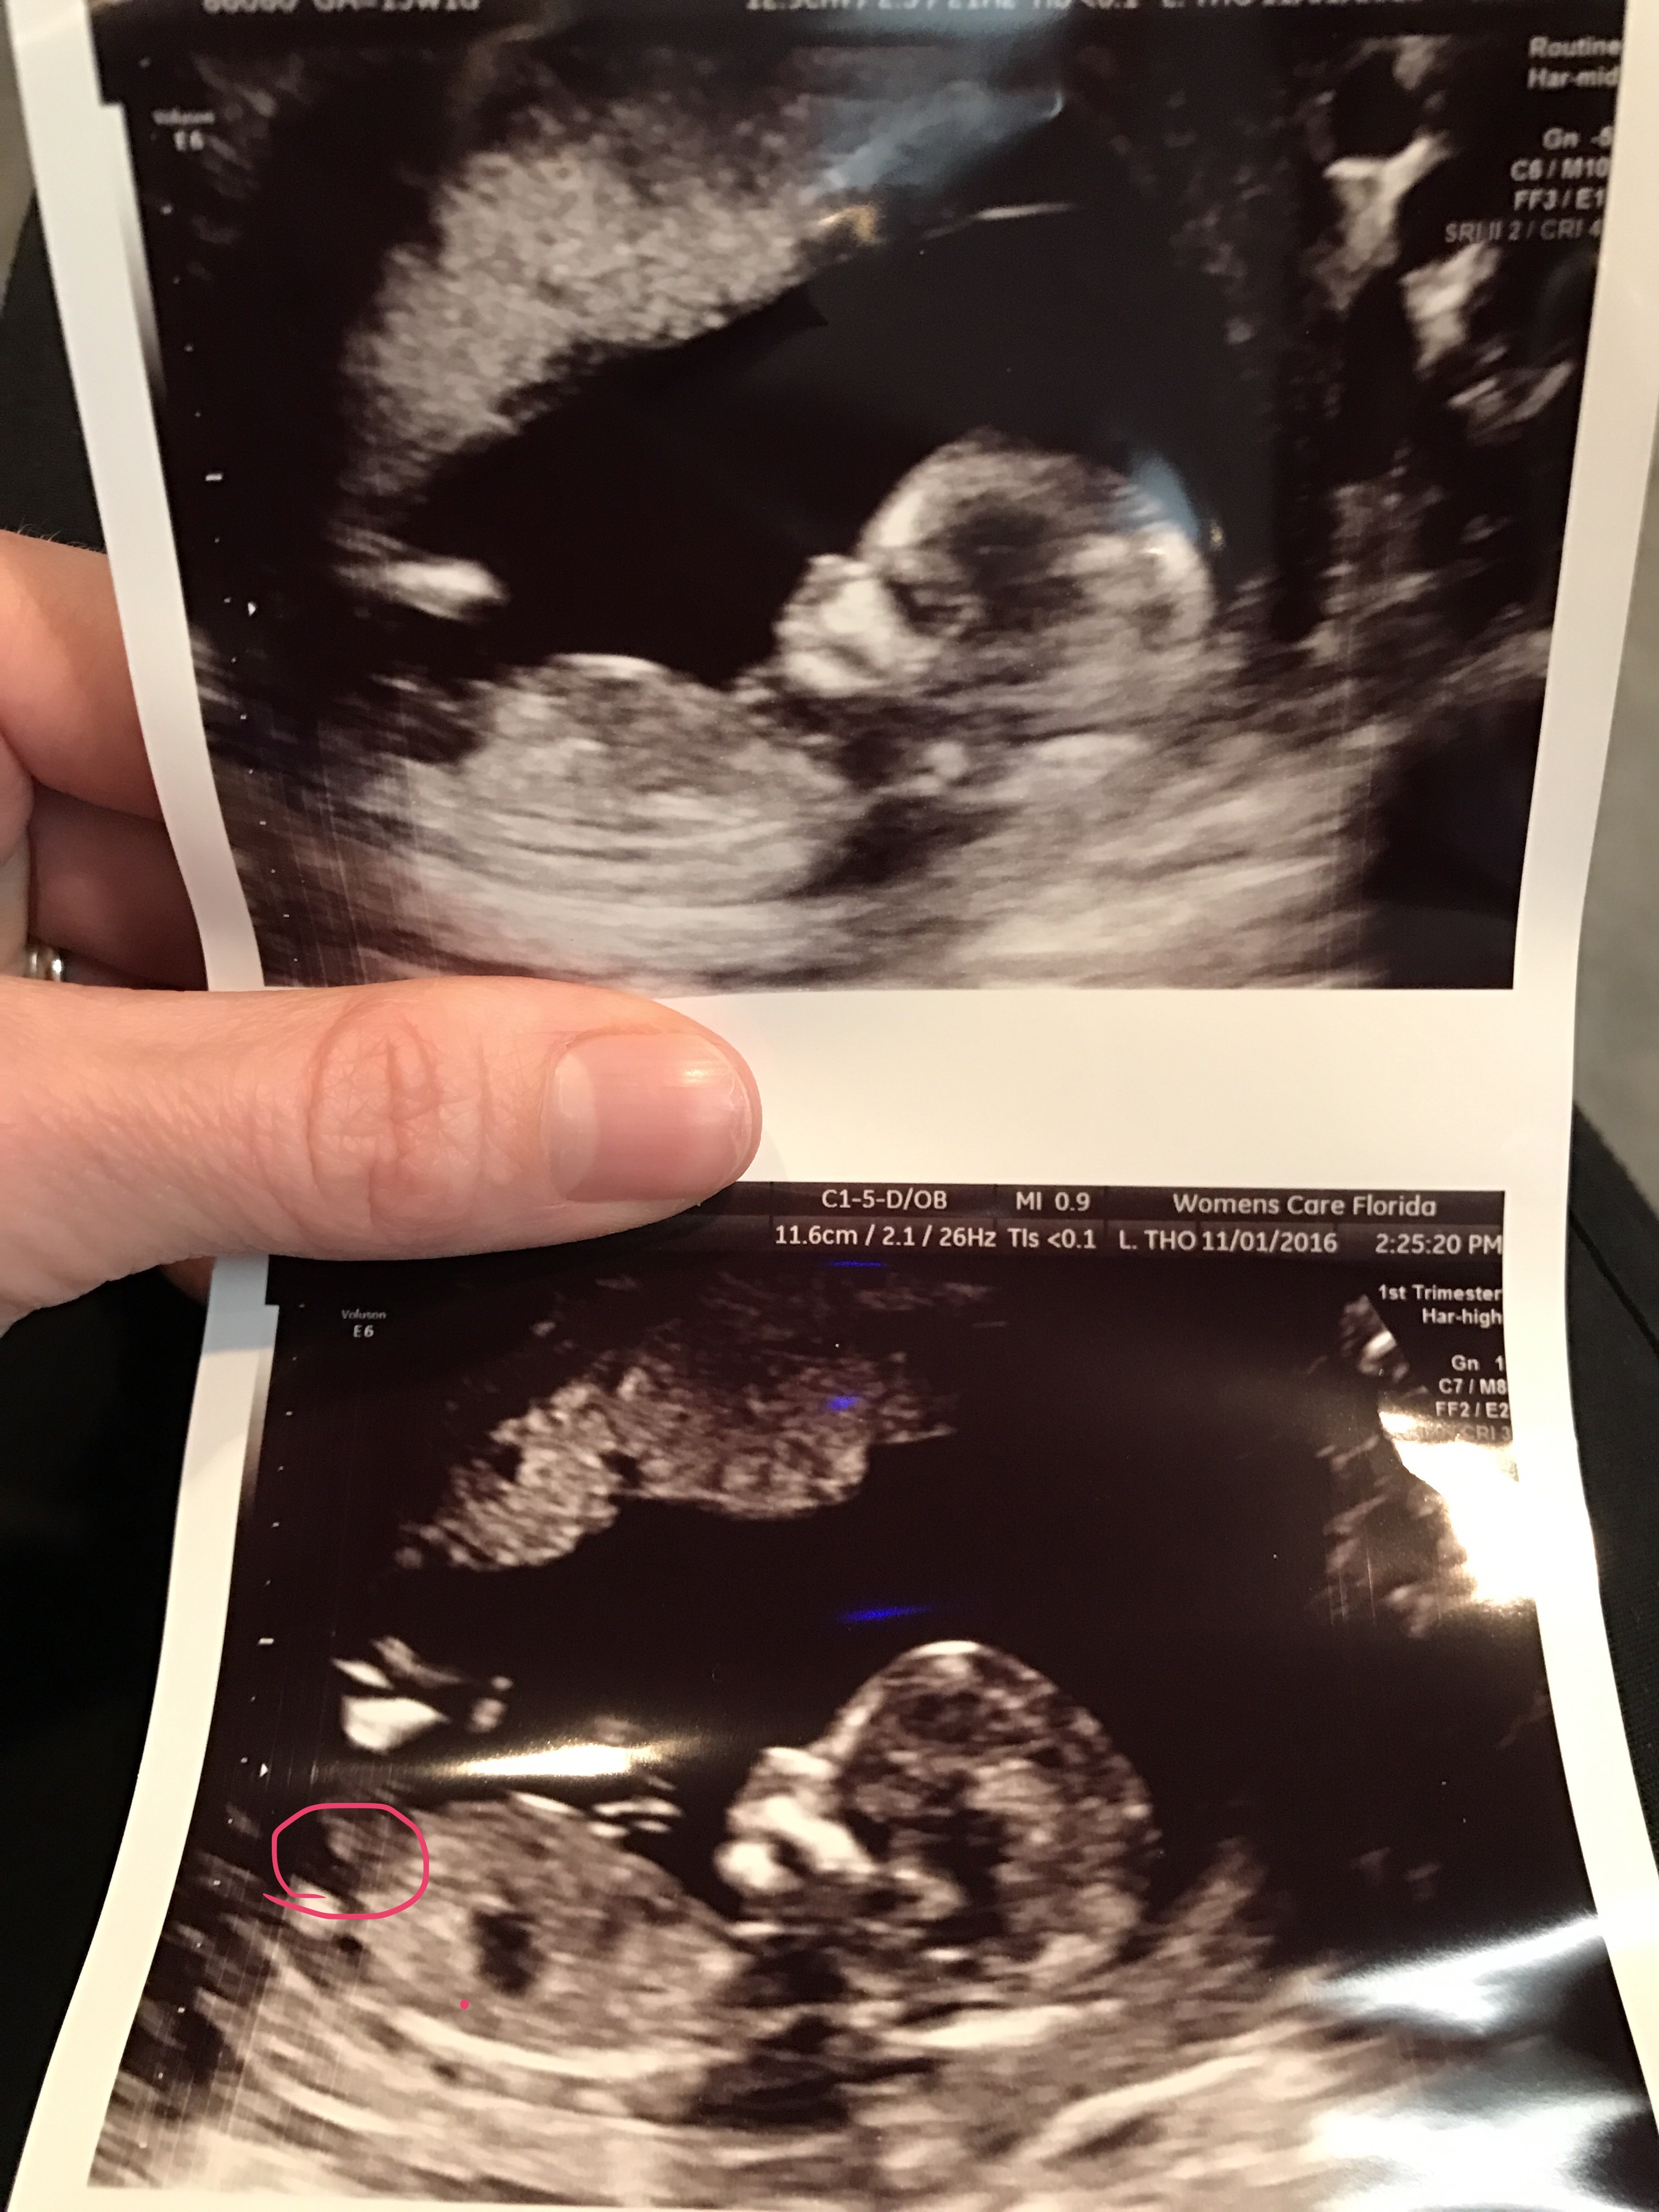

I circled in pink what I think is the nub in the bottom picture.Attachment 33599